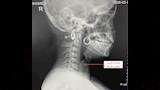

واستقبل قسم الاستقبال والطوارئ بالمستشفى المريضة وهي تعاني من آلام شديدة في الرقبة وصعوبة حادة في التنفس، وعلى الفور تم إجراء الفحوصات والأشعة اللازمة التي أكدت استقرار الدبوس في منطقة دقيقة بمدخل مجرى التنفس، ما شكّل خطورة على حياتها.